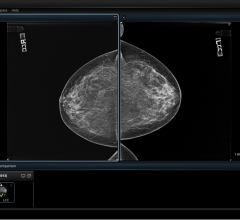

Looking for signs of cancer in the mammogram of a dense breast is like looking for a polar bear in a snowstorm. Because they absorb X-rays, glandular and fibrous tissue appear white, as do microcalcifications, lumps and other lesions that may indicate breast cancer.

The practice of breast imaging and screening in women at risk for breast cancer is evolving as new imaging modalities are incorporated and researchers continue to study the implications of dense breast tissue in patients. At the 2013 annual meeting of the Radiological Society of North America (RSNA) in Chicago, there were several sessions highlighting trials and studies that brought breast density and cancer detection to the forefront.

Despite decades of progress in breast imaging, one challenge continues to test even the most skilled radiologists ...

St. Peter’s Breast Center, located in Albany, N.Y, added 3D mammography (breast tomosynthesis) in 2011 because the staff knew it would improve diagnostic accuracy; even so, the technology has exceeded all expectations. In 2012 more than 22,000 mammograms were performed at the breast center.

To help identify trends and find out what topics Imaging Technology News (ITN) readers are interested in, our editorial team makes note of what the audience is viewing online at itnonline.com. In 2013, the topic of women’s breast health — specifically, breast density — dominated half of this list. Perhaps 2014 will be the year that standardized breast density reporting will become law in all states; 2013 got this off to a good start, helping to spread awareness. Other hot topics included healthcare reform and the role it could play in the radiology field, and of course breaking new technology.